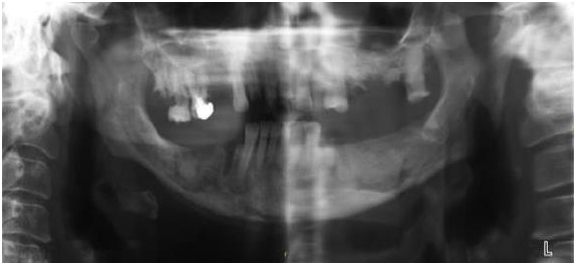

Figure 2 shows the respected portion of the mandibulary bone and Figure 3 shows the reconstructed mandible and Figures 4 & 5 the end cosmetic result. At the present time (9 months after the procedure), the patient’s metastatic disease is still under control with hormone therapy. After a smooth post-operative course, her maxillary bone is healed and she is being prepared to receive dental implants (Figure 4).

Figure 3 Reconstruction with a left fibula free flap (November 8, 2016).